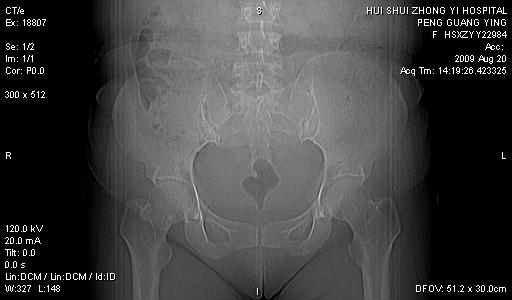

标题: CT21707:女,42岁,因发现下腹部包块2月。 [打印本页]

标题: CT21707:女,42岁,因发现下腹部包块2月。

病灶来源——子宫?附件?

从平扫角度看本人还是倾向于子宫肌瘤诊断,宫腔少量积液。

目前的影像表现显示肿块位于腹腔及盆腔,但具体定位,分清来源较困难,是否来源于卵巢、子宫无法定论,子宫直肠及子宫膀胱周围脂肪间隙尚较清晰,如果患者有过腹腔好或者盆腔手术史,也可以形成不典型的血中,最好手术后定为定性,我期待结果。

软组织密度,与子宫一致。双侧卵巢形态、密度好,不支持来源于卵巢。

病史不全面,病灶来源可能是子宫或卵巢,若临床有剖腹产、痛经史,则更支持前者,亦更支持子宫腺肌症